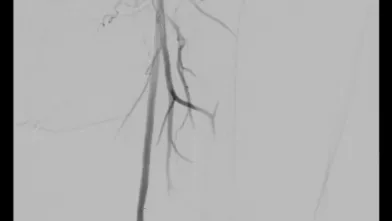

本症例は、初回治療2年後フォローアップ時のエコー所見から、DESの中枢および末梢の病変が閉塞の原因となった可能性が高い。同部位はDCBおよびDESで治療されているにもかかわらず、2年で再狭窄を呈していることから、drug technologyを用いたバルーンおよびステントでの治療は許容できないと判断した。BMI 31.9の肥満であったため右総大腿動脈より対側山越アプローチとした。6 Fr 45 cmガイディングシース + 5.5 Frシースバックアップ下に血管内超音波(IVUS)ガイドで臨んだ。エコー所見どおりDESの中枢および末梢病変は非常に強固であったため、ガイドワイヤー(40 g)で通過した。DES内の病変は非常に柔らかく、ガイドワイヤー(1 g)で通過、DCBのステント内閉塞はガイドワイヤー(15 g)を用い、IVUS下に確実に真腔内で通過した。0.014 inchガイドワイヤーの場合、ガイドワイヤーはステントストラットを容易に通過する。そのため、複数方向からの透視やIVUSを用いることで、確実にステント内を通過していることを確認することが必要となる。また、ステント内はhealthy landingではないことから、確実に前回のステントを最低1 cm以上越えて留置すべきである。DESの再狭窄は、culprit以外が柔らかい赤色血栓であることが多く、この症例もガイドワイヤーの感覚から同様の所見が疑われた。末梢塞栓予防に造影カテーテルによる可及的血栓吸引を行い、バルーン4.0 mm × 300 mmで前拡張をした。末梢病変はバイアバーン® ステントグラフト6 mm × 150 mmを留置、中枢は左浅大腿動脈起始部から10 mmのhealthy landingが残存していたため、同部位よりステントグラフト6 mm × 150 mmを留置した(図1)。高耐圧バルーン6.0 mm × 150 mmで後拡張を行い(図2、図3)、十分にgainを確保し良好なflowで終了した。治療時間は40分、造影剤使用量は70 mL であった。